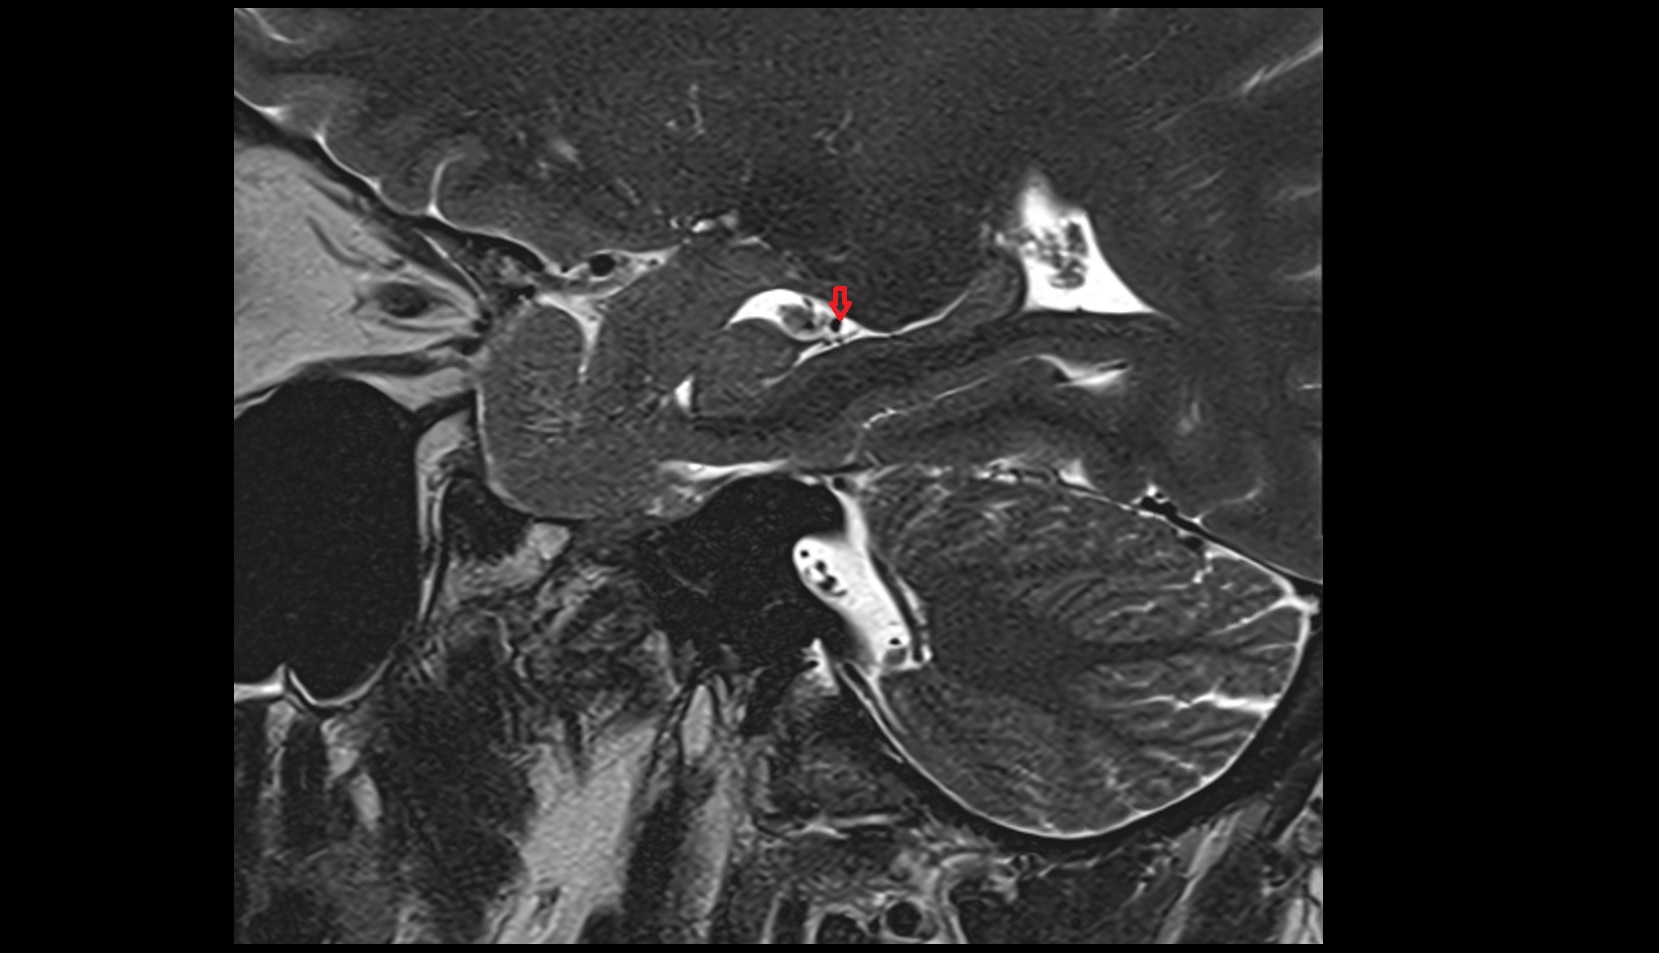

- Temporomandibular joint

- Articular disc of temporomandibular joint

- Articular eminence

- Mandibular condyle

- Mandibular fossa